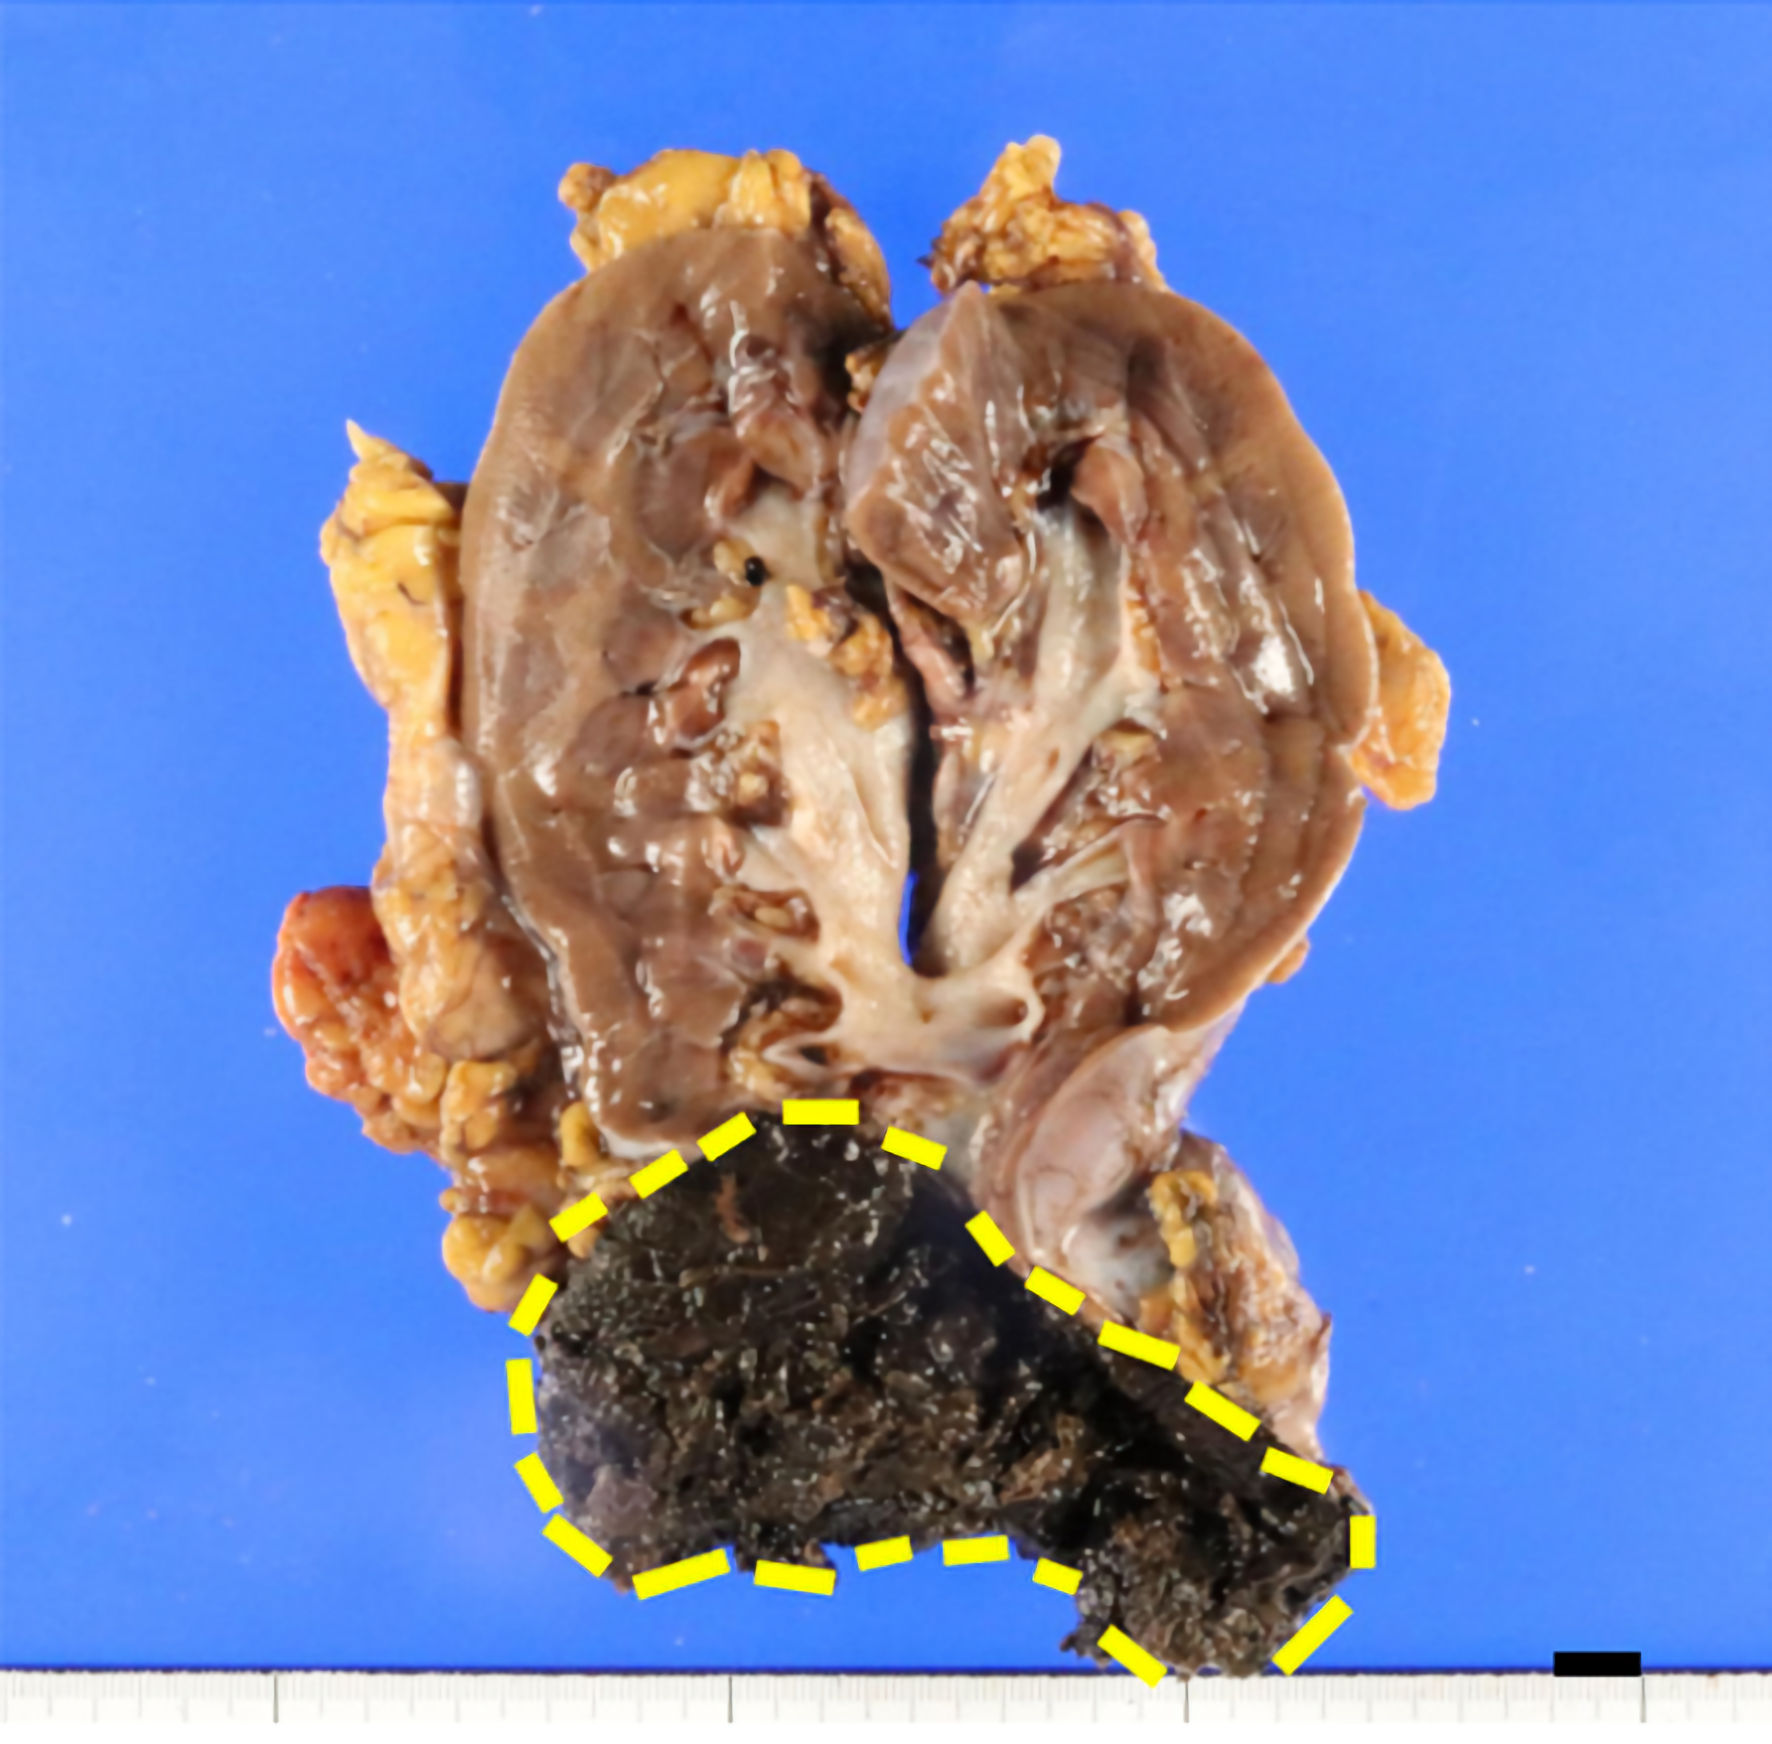

Grossly, a tumor (7 cm in diameter) in the right kidney had a dark-brown split, suggesting degeneration and necrosis of the tumor (Fig. 2). Histologically, the tumor was well demarcated by a thickened fibrous capsule (Fig. 3a). Papillary growth of tumor cells with spongiotic or eosinophilic cytoplasm and prominent nucleoli was observed. They possessed a dark-brown pigment in their cytoplasm (Fig. 3b). There was no evidence of vascular or lymphatic invasion. Immunohistochemistry revealed that the tumor cells were positive for Melan A (Fig. 4a), human melanoma black 45 (HMB45) (Fig. 4b), and soluble 100 protein (S-100) (Fig. 4c) but negative for transcription factor E3 (TFE3) (Fig. 5a), transcription factor EB (TFEB) (Fig. 5b), cytokeratin 7 (CK7) (Fig. 5c), carbonic anhydrase 9 (CA9) (Fig. 5d), and AE1/AE3.

![]() Click for large image | Figure 2. Grossly, the cut surface of the tumor (7 cm in diameter), surrounded by a dashed line, was dark brown in color. The distance between the tumor and the renal pelvis is 1 cm (scale bar (black): 10 mm). |